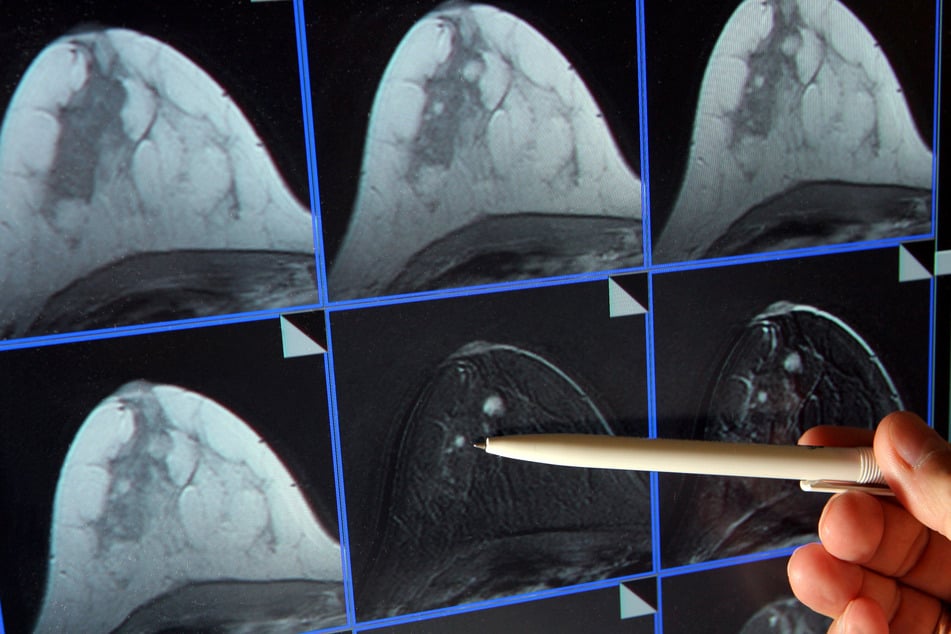

Häufigste Krebserkrankung bei Frauen: Vorsorge-Angebot sollte deutlich mehr genutzt werden

Düsseldorf - Ärztevereinigungen rufen Frauen dazu auf, das Mammographie-Screening zur Brustkrebsvorsorge noch stärker als bislang zu nutzen.

Brustkrebs ist den Angaben zufolge die häufigste Krebserkrankung bei Frauen. Jede achte Frau in Deutschland sei im Laufe ihres Lebens von dieser Erkrankung betroffen. Für 18.500 Frauen pro Jahr ende die Erkrankung tödlich.

Das Mammographie-Screening-Programm steht für Frauen ab 50 bis 75 Jahren in ganz Deutschland zur Verfügung, wie die beiden Kassenärztlichen Vereinigungen zu dem Vorsorgeangebot erläuterten.